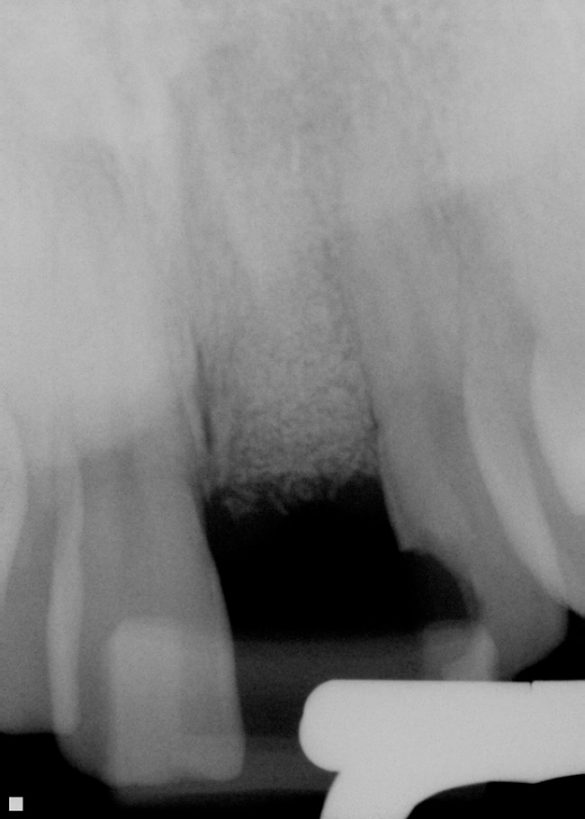

Din cele 109 implante inserate la cei 69 pacienţi în cursul unei perioade de 4 ani, nu s-a înregistrat niciun eşec implantologic după inserţia dispozitivelor fixe şi restaurarea protetică ulterioară. La descoperirea implantelor, nu erau semne de mobilitate a acestora, şi toate implantele inserate au fost restaurate. În momentul prelucrării datelor, toate implantele au rămas complet încărcate şi în funcţiune, rezultând o rată de supravieţuire de 100% (tabelul 1). Ca şi grup, implantele erau funcţionale şi încărcate de o perioadă medie de 2 ani, variind între 6-65 luni. Indiferent de tipul implantului, localizarea în alveolă, statusul de fumător, 100% din implante sunt în funcţiune şi actualmente (tabelul 1 şi fig. 1-9).

Alveolele postextracţionale au fost lăsate să se vindece pentru o perioadă medie de 6 luni. După vindecare, s-au inserat în total 109 implante. Nu s-au înregistrat eşecuri de grefare şi implantele au fost aplicate în toate cele 109 locaţii grefate. Un total de 58 de implante au fost introduse cu reflecţia lamboului, iar 51 cu tehnica fără lambou/prin perforare. S-au folosit implante endoosoase într-o singură etapă şi în două etape, reprezentând diferite forme de implante. Diametrele implantelor au variat de la 3,3mm până la 5mm, cu lungimea implantelor variind între 10-15mm, în funcţie de consideraţiile restauratoare şi localizările în cadrul alveolelor. Toate implantele inserate aveau design cu suprafaţă rugoasă. Din cele 109 implante inserate, 67 au fost aplicate la maxilar şi 42 la mandibulă. Un total de 33 de implante au fost inserate la fumători (11 pacienţi) şi 76 de implante la nefumători (58 pacienţi).